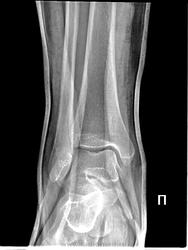

как вариант, остеохондральный (субхондральный) перелом.

но на мой взгляд представленный случай на "Диаза" мало похож...

Возможно корректнее можно говорить о посттравматическом или аваскулярном некрозе.

У меня впечатление, что скиалогическая это "тенюха". Видим мы её и на первом снимке, только +гипс, +некоторый минимальный поворот - и, как сказал один коллега - вуаля!))

Это на нашей пленочной классике - вуаля! (vega ©), а на этой цифре - не кажется контурообразующим краем. Похоже на кортикальный осколок (тут капсула крепится). Тем более виден на обоих снимках. По таранной- согласен с постом №1, т.к. деформация (импрессия) кортекса имеется и на первичном и на контрольном снимке, вряд-ли некроз.